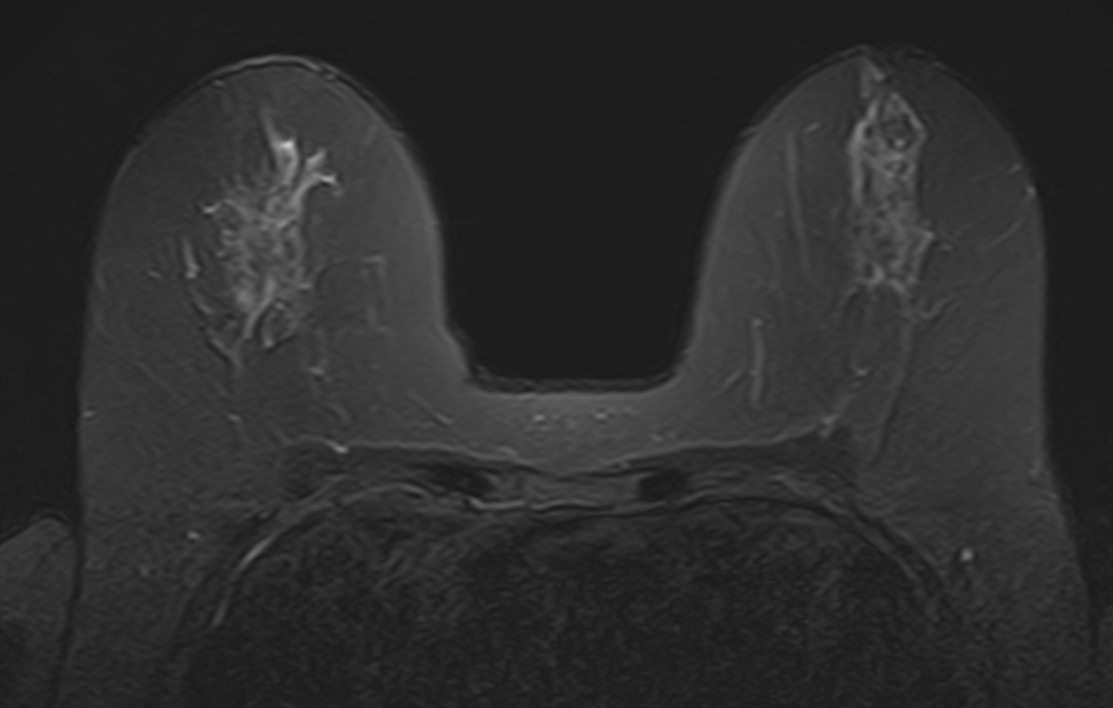

Выполнение МРТ молочных желез без контрастирования возможно для динамического наблюдения состояния имплантатов после пластической операции груди. Во всех остальных случаях во время проведения исследования внутривенно вводится контрастное вещество. Для контрастного усиления применяются препараты на основе солей гадолиния (Магневист, Гадовист и др).

- Для оценки состояния силиконовых имплантов после пластики груди;